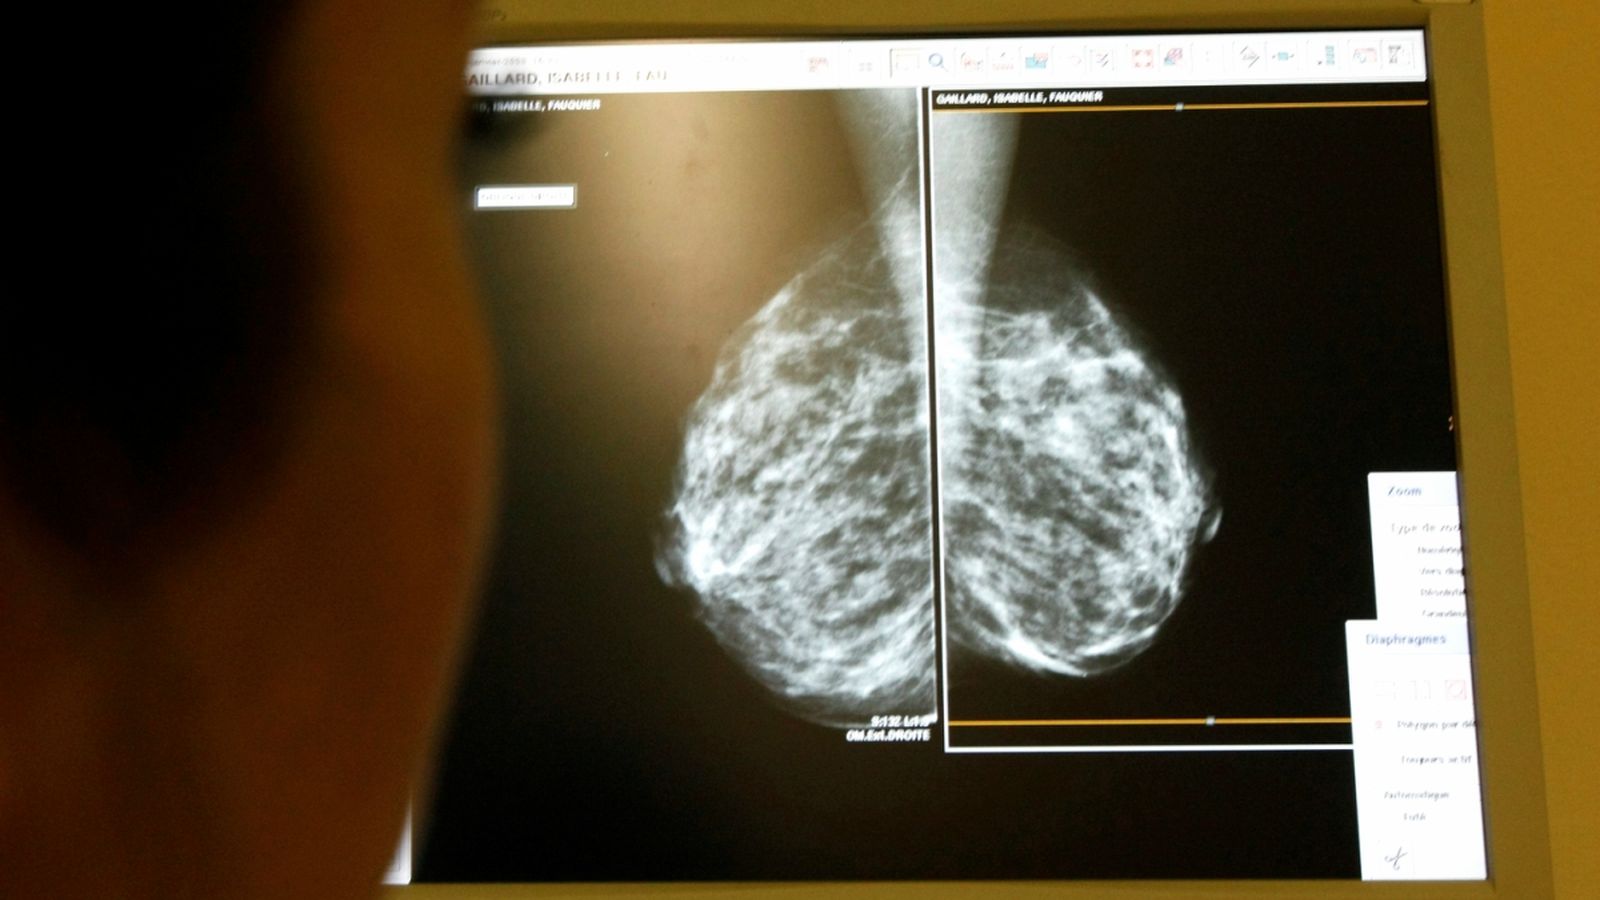

Gran errada en les mamografies a Anglaterra

Fins a 270 dones angleses podrien haver perdut la vida per una errada informàtica en els avisos de mamografia.

Més de 450.000 dones angleses s'han quedat sense fer-se la mamografia que, segons la normativa sanitària britància, havien d'haver-se fet entre 2009 i 2018.

Ho ha reconegut el ministre britànic de Sanitat, Jeremy Hunt, qui ha atribuït a la informàtica una errada que pot haver costat la vida a 270 dones. Al Regne Unit, totes les dones entre 50 i 70 anys poden fer-se una mamografia cada tres anys per tal de detectar a temps un possible càncer de pit. El Ministeri de Sanitat envia les cartes, però sembla que hi va haver alguna classe d'errada en el programa informàtic que emet les comunicacions pesonalitzades.